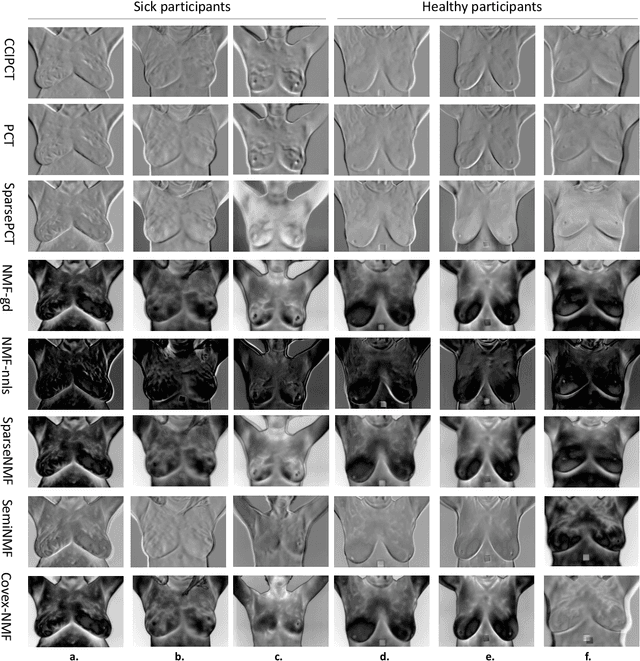

Abstract:The early detection of breast abnormalities is a matter of critical significance. Notably, infrared thermography has emerged as a valuable tool in breast cancer screening and clinical breast examination (CBE). Measuring heterogeneous thermal patterns is the key to incorporating computational dynamic thermography, which can be achieved by matrix factorization techniques. These approaches focus on extracting the predominant thermal patterns from the entire thermal sequence. Yet, the task of singling out the dominant image that effectively represents the prevailing temporal changes remains a challenging pursuit within the field of computational thermography. In this context, we propose applying James-Stein for eigenvector (JSE) and Weibull embedding approaches, as two novel strategies in response to this challenge. The primary objective is to create a low-dimensional (LD) representation of the thermal data stream. This LD approximation serves as the foundation for extracting thermomics and training a classification model with optimized hyperparameters, for early breast cancer detection. Furthermore, we conduct a comparative analysis of various embedding adjuncts to matrix factorization methods. The results of the proposed method indicate an enhancement in the projection of the predominant basis vector, yielding classification accuracy of 81.7% (+/-5.2%) using Weibull embedding, which outperformed other embedding approaches we proposed previously. In comparison analysis, Sparse PCT and Deep SemiNMF showed the highest accuracies having 80.9% and 78.6%, respectively. These findings suggest that JSE and Weibull embedding techniques substantially help preserve crucial thermal patterns as a biomarker leading to improved CBE and enabling the very early detection of breast cancer.

Abstract:Thermography has been used extensively as a complementary diagnostic tool in breast cancer detection. Among thermographic methods matrix factorization (MF) techniques show an unequivocal capability to detect thermal patterns corresponding to vasodilation in cancer cases. One of the biggest challenges in such techniques is selecting the best representation of the thermal basis. In this study, an embedding method is proposed to address this problem and Deep-semi-nonnegative matrix factorization (Deep-SemiNMF) for thermography is introduced, then tested for 208 breast cancer screening cases. First, we apply Deep-SemiNMF to infrared images to extract low-rank thermal representations for each case. Then, we embed low-rank bases to obtain one basis for each patient. After that, we extract 300 thermal imaging features, called thermomics, to decode imaging information for the automatic diagnostic model. We reduced the dimensionality of thermomics by spanning them onto Hilbert space using RBF kernel and select the three most efficient features using the block Hilbert Schmidt Independence Criterion Lasso (block HSIC Lasso). The preserved thermal heterogeneity successfully classified asymptomatic versus symptomatic patients applying a random forest model (cross-validated accuracy of 71.36% (69.42%-73.3%)).

Abstract:Active and passive thermography are two efficient techniques extensively used to measure heterogeneous thermal patterns leading to subsurface defects for diagnostic evaluations. This study conducts a comparative analysis on low-rank matrix approximation methods in thermography with applications of semi-, convex-, and sparse- non-negative matrix factorization (NMF) methods for detecting subsurface thermal patterns. These methods inherit the advantages of principal component thermography (PCT) and sparse PCT, whereas tackle negative bases in sparse PCT with non-negative constraints, and exhibit clustering property in processing data. The practicality and efficiency of these methods are demonstrated by the experimental results for subsurface defect detection in three specimens (for different depth and size defects) and preserving thermal heterogeneity for distinguishing breast abnormality in breast cancer screening dataset (accuracy of 74.1%, 75.8%, and 77.8%).